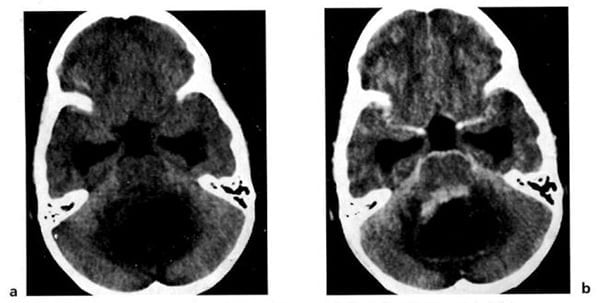

Hình 1.54. U tế bào hình sao (độ 1) ở tiểu não của một trẻ 5 tuổi. Trước tiêm (a), u có mật độ thấp và hiện lên như dạng nang hoàn toàn. Sau tiêm (b), phần đặc bắt chất cản quang.

Hình 1.55. U tế bào hình sao (độ 2) ở một trẻ 2 tuổi. Trước tiêm (a), u có mật độ thấp đặc trưng (mũi tên). Thành phần đặc bắt rõ chất cản quang (b). Não úng thủy do tắc nghẽn.